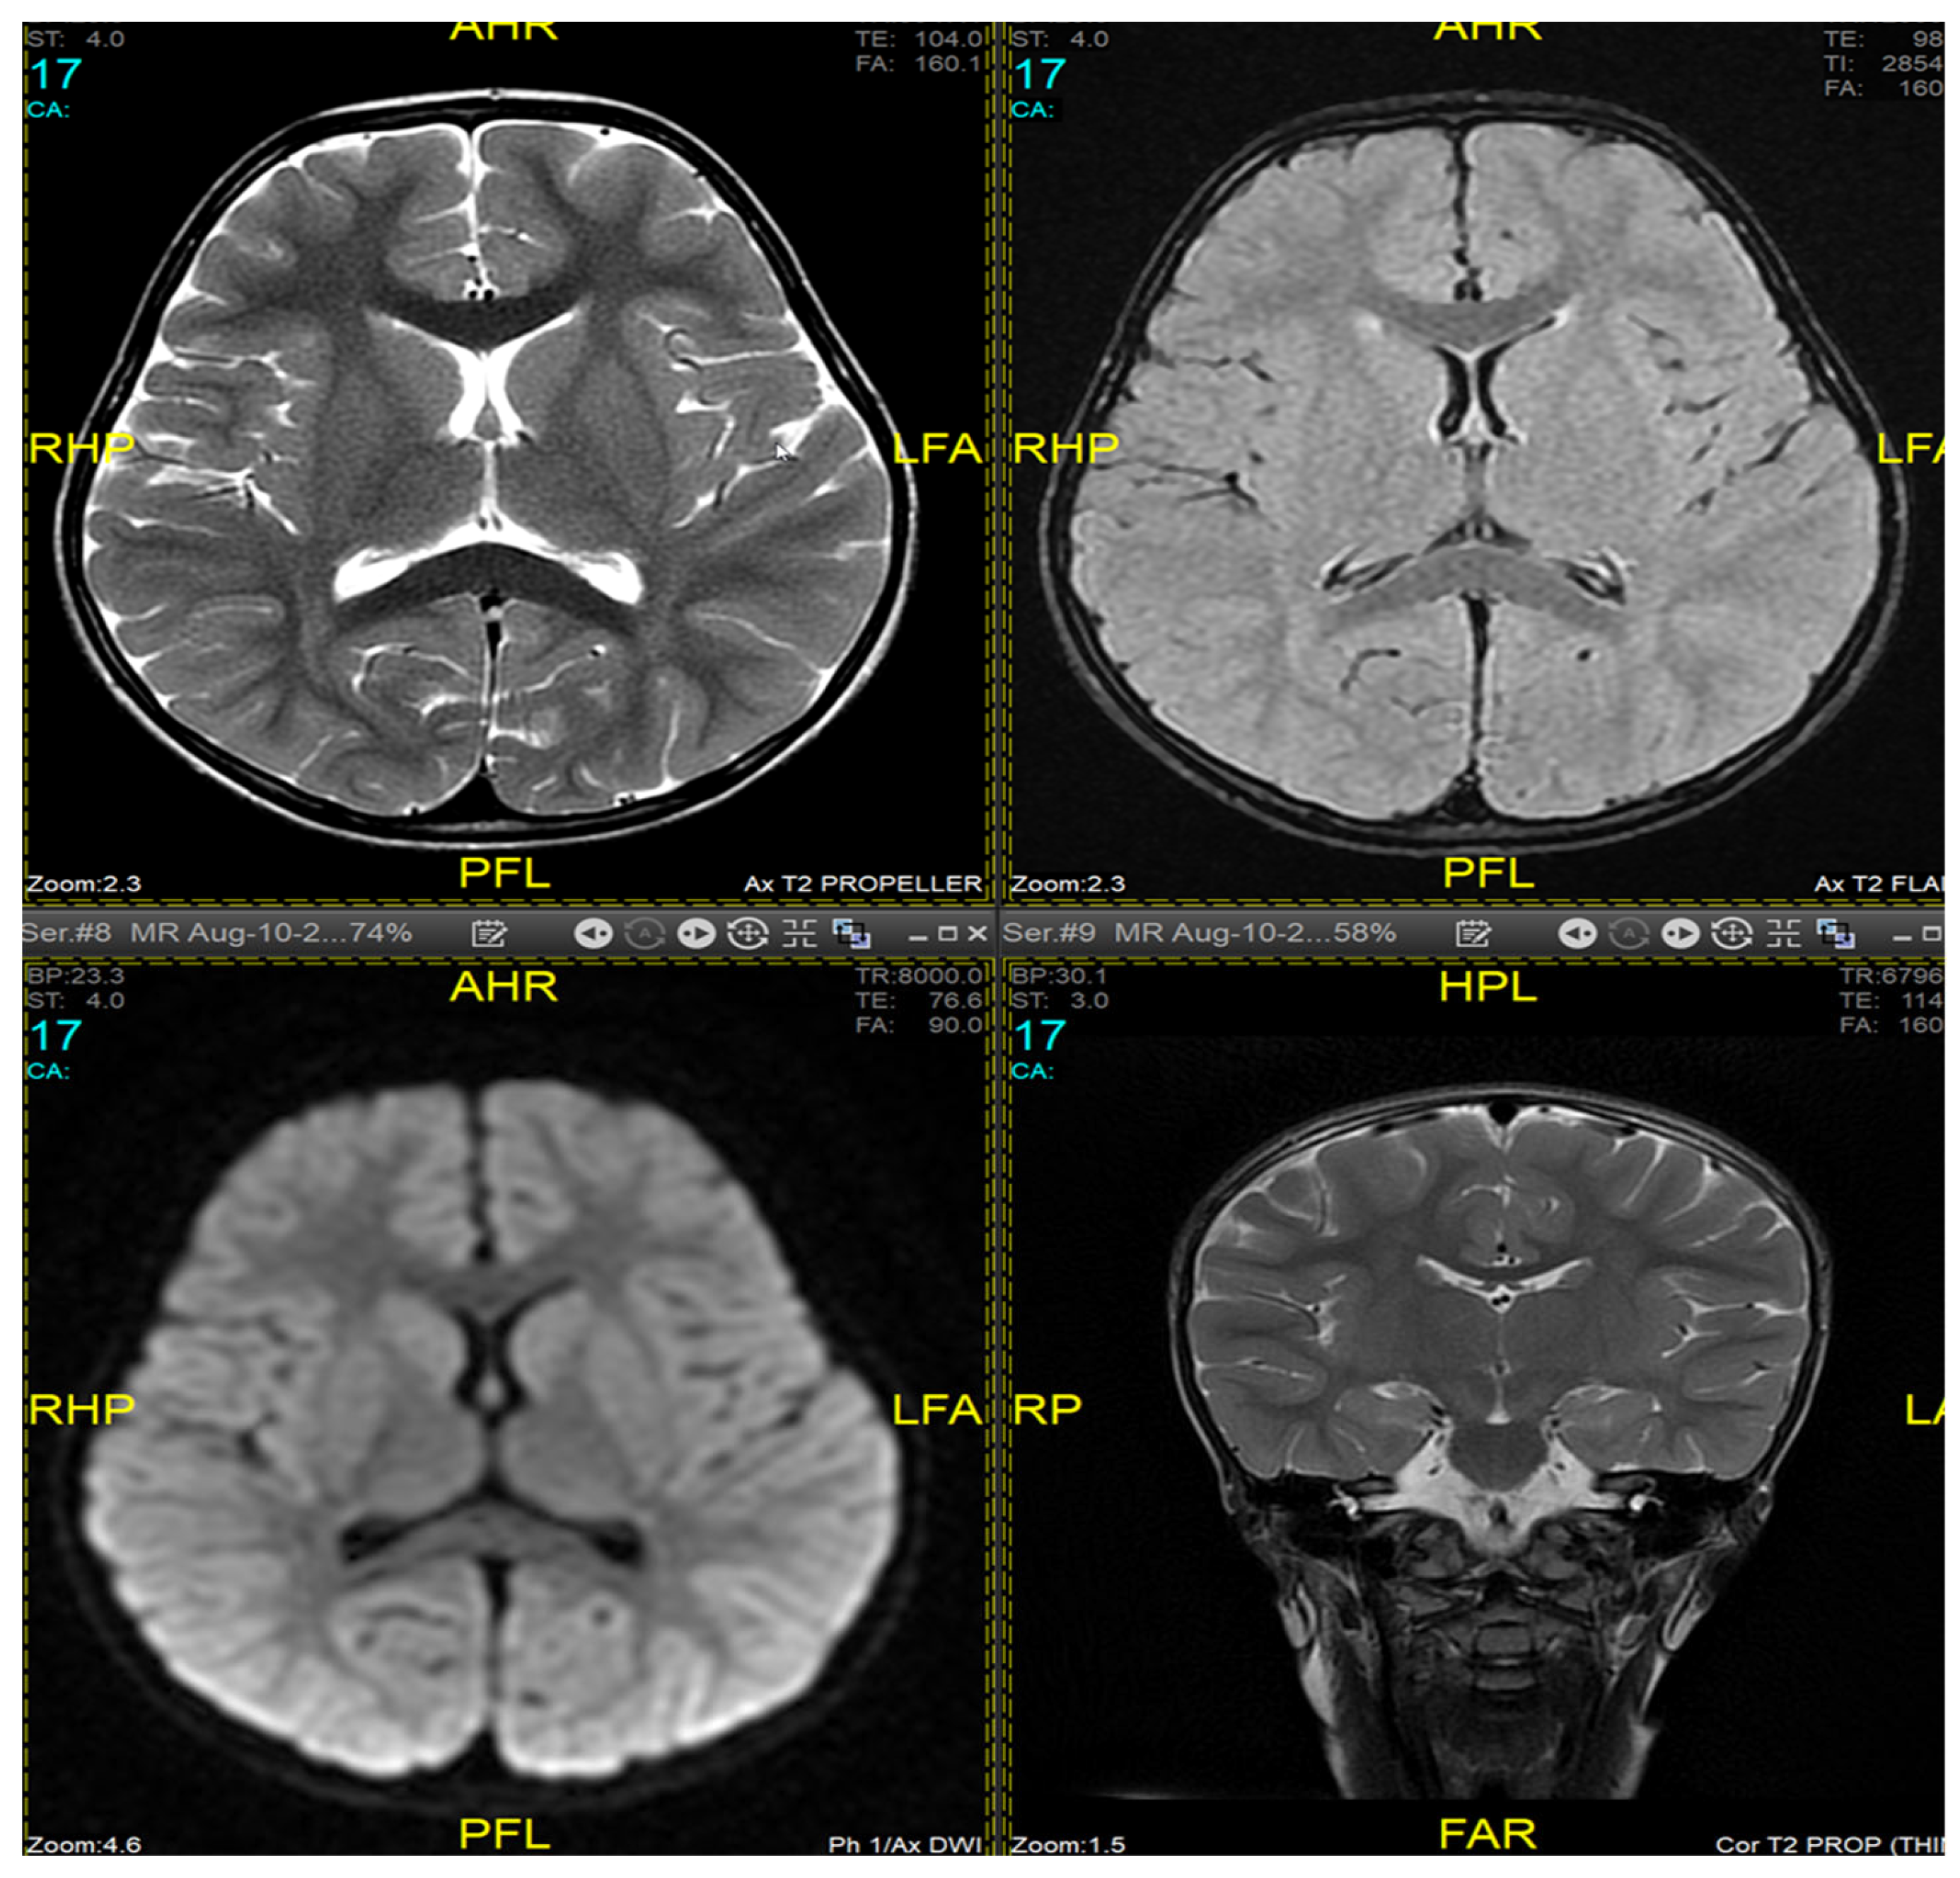

Magnetic resonance imaging (MRI) of the brain and genetic analysis were done to support the diagnosis. Her MRI now showed newly developed generalized atrophic changes of the brain, characterized by supra and infratentorial ventricular dilatation, prominent cortical sulci, and extra-axial CSF spaces such as Sylvian fissures and basal cistern. The diffuse deep periventricular white matter showed high signal intensities on T2/FLAIR (Fluid Attenuated Inversion Recovery) sequences. Additionally, there was global thinning out of the corpus callosum [Figure 1]. This was in contrast to her prior brain MRI at the age of 2.5 years which showed no evidence of atrophic brain changes or iron deposition [Figure 2].

MRI findings are variable depending on the disease stage at which imaging was performed [1,3,9,11]. Imaging may be completely normal in some patients, as was the case in our patient during the first presentation, making it insufficient to rule out INAD based on radiological findings only and necessitating follow up imaging later. Typical findings described include cerebral atrophy, white matter changes, and iron deposits in the globus pallidus, substantia nigra, and dentate nucleus [18,19]. Due to the presence of iron deposits, INAD can be classified as a subtype of neurodegeneration with brain iron accumulation diseases (NBIA). However, iron deposits are not specific to INAD [20]. Our patient exhibited typical MRI features, on a follow-up study, but did not have any evidence of iron accumulation in the brain.

Figure 2. Bain MRI at the age of 2.5 years (10 August 2017) - No evidence of atrophic brain changes or iron deposition.